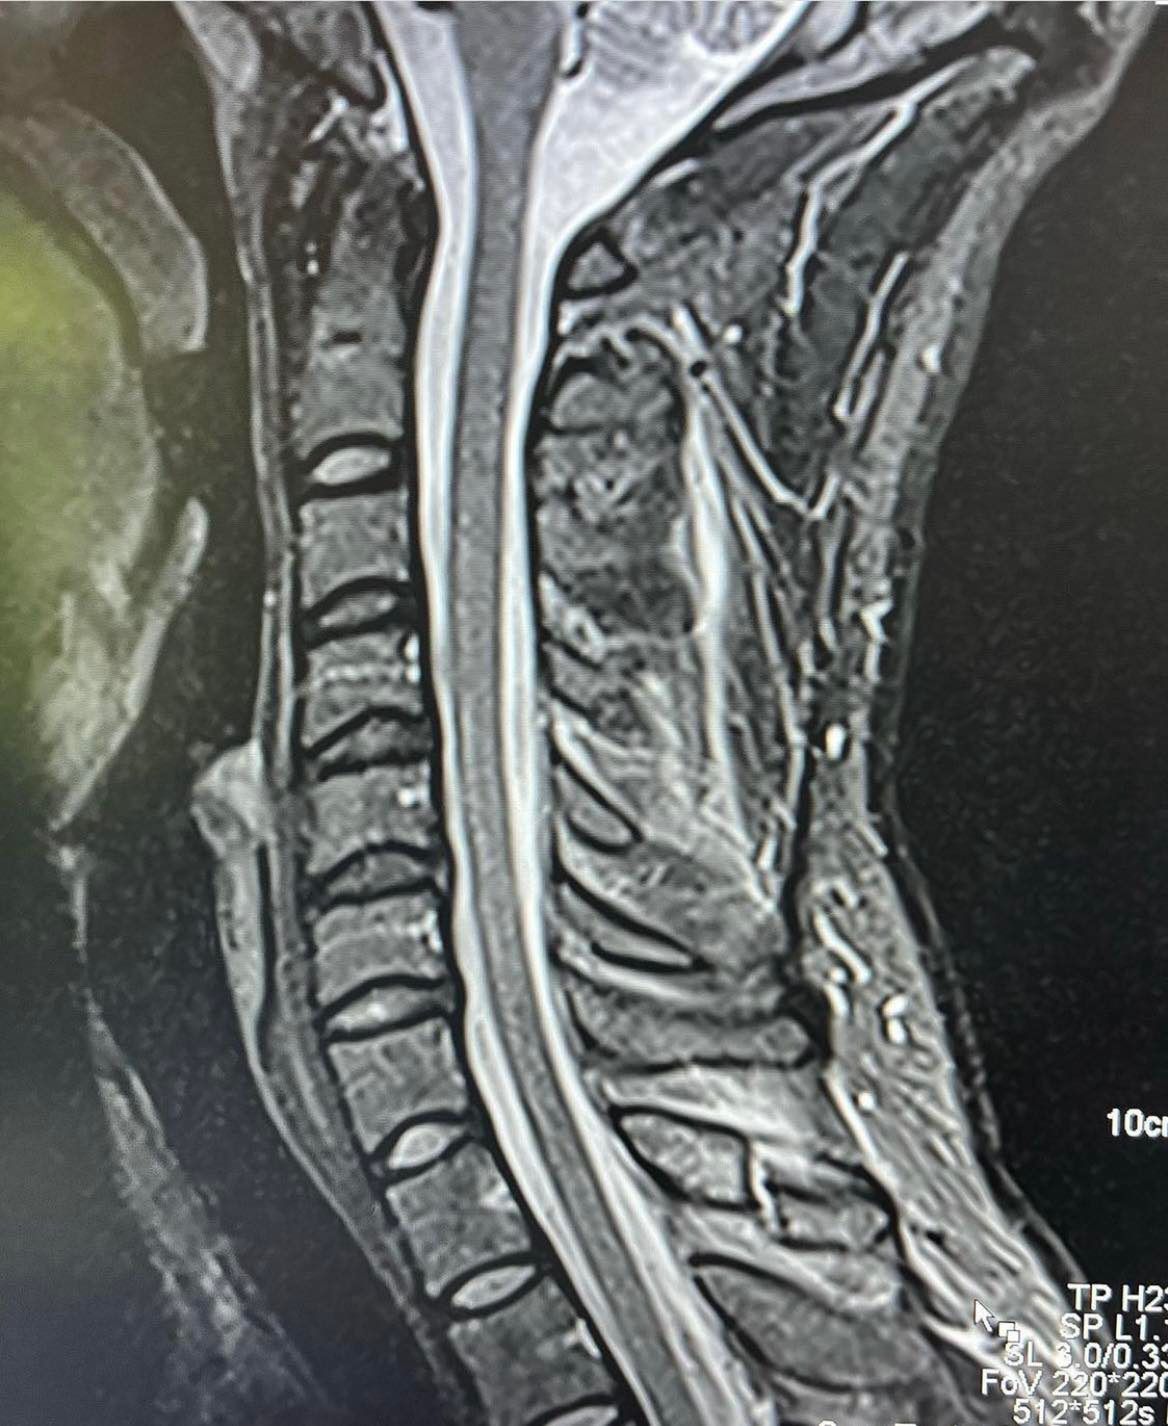

Dla tych, którzy chcieli zobaczyć, jak ukochany Agnieszki Włodarczyk poradzi sobie w oktagonie podczas 14. edycji słynnej gali, mamy złą wiadomość. Okazuje się, że Robert był zmuszony wycofać się z walki z Adamem Josefem ze względu na poważną kontuzję. W poniedziałek triathlonista wrzucił do sieci zdjęcie rentgenowskie odcinka szyjnego kręgosłupa, a także takie, gdzie widać na jego szyi kołnierz ortopedyczny. Dokładnym powodem wykluczenia z rywalizacji jest złamanie wyrostka kolczystego.